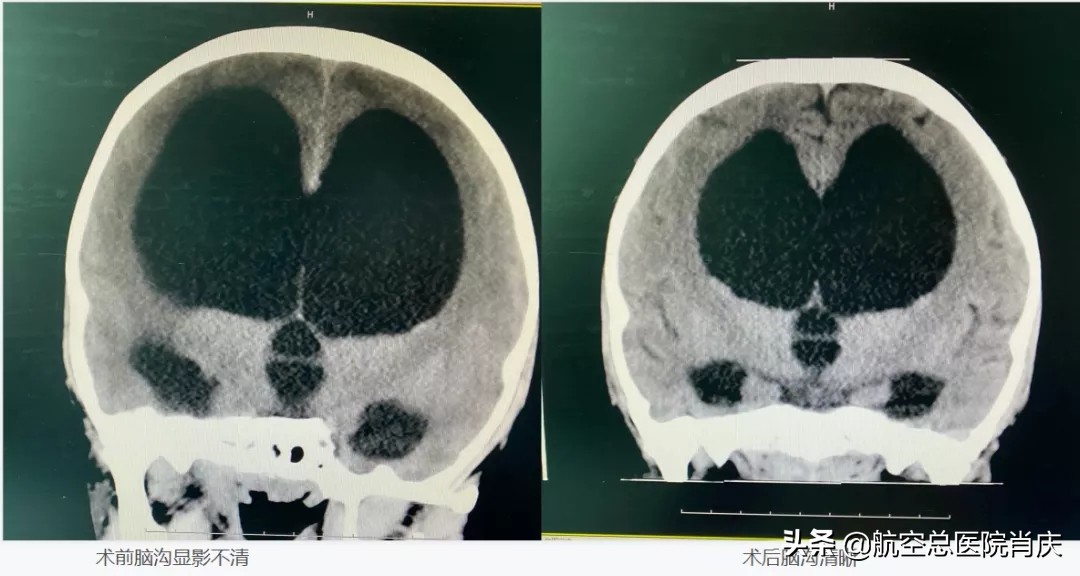

肖庆主任决定给小女孩一次不带管的机会,运用神经内镜软镜技术,探查脑室,明确脑室内情况,酌情行第三脑室底造瘘术,重建脑脊液内循环,借助基底动脉搏动进一步改变脑脊液循环动力,但由于患者长期高颅压状态,脑顺应性差,在脑积水解除后,原受压脑实质的功能能否得以恢复,仍需远期观察病情变化,家长对此表示理解。

这样的患者经肖庆主任之手每年可治愈百余例,在各职能部门紧张有序配合下,手术进行得非常顺利。术后小患者意识恢复,神志清醒,精神状态良好,四肢活动自如,家长脸上也终于露出了笑容,不断的说孩子的病情一天比一天好了。